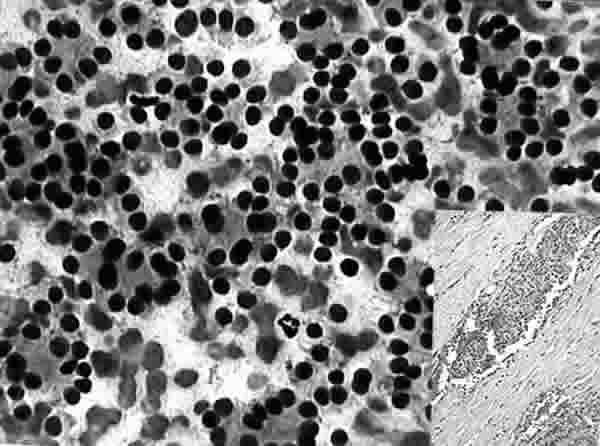

Fig. 1. PAAF de Tiroides. Giemsa-QCA. x200. Proliferación Folicular. Microfolículos. Recuadro inferior: Tejido. HE. x100. Carcinoma Folicular. Invasión linfática capsular.